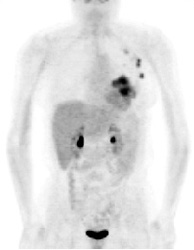

PET exam for the evaluation of locoregional recurrence: The patient shown in the case below had a history of breast cancer and had developed left chest pain. She presented for the evaluation of possible metastatic disease. The CT scan revealed extensive soft tissue thickening in the left breast which was felt possibly related to scar from prior surgery and radiation therapy. There was a 2 cm lymph node in the left axilla (not shown) which was concerning for metastatic disease. Axial (center) and coronal (right) images from the patients FDG PET exam demonstrated marked increased FDG accumulation within the left breast corresponding to the soft tissue abnormality on CT. There were also multiple foci of increased uptake within the the left axilla. Biopsy revealed recurrent breast cancer.